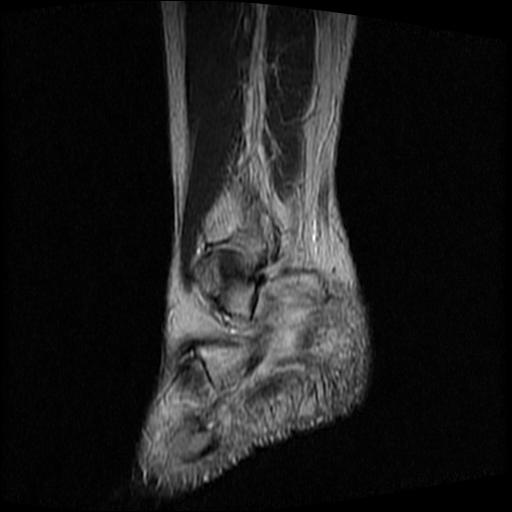

标题: MRI0968:女性,70岁,跟骨信号异常 [打印本页]

标题: MRI0968:女性,70岁,跟骨信号异常

女性,70岁,右侧跟骨疼痛2个月,负重时加剧,不负重时不疼。

胫骨下段,跟骨、距骨可见斑片状异常信号区;考虑:转移瘤

跟骨长t1长t2信号异常,边缘模糊(肿瘤一般边界清楚,故肿瘤不考虑),压脂像呈高信号--骨髓水肿(炎症?)。